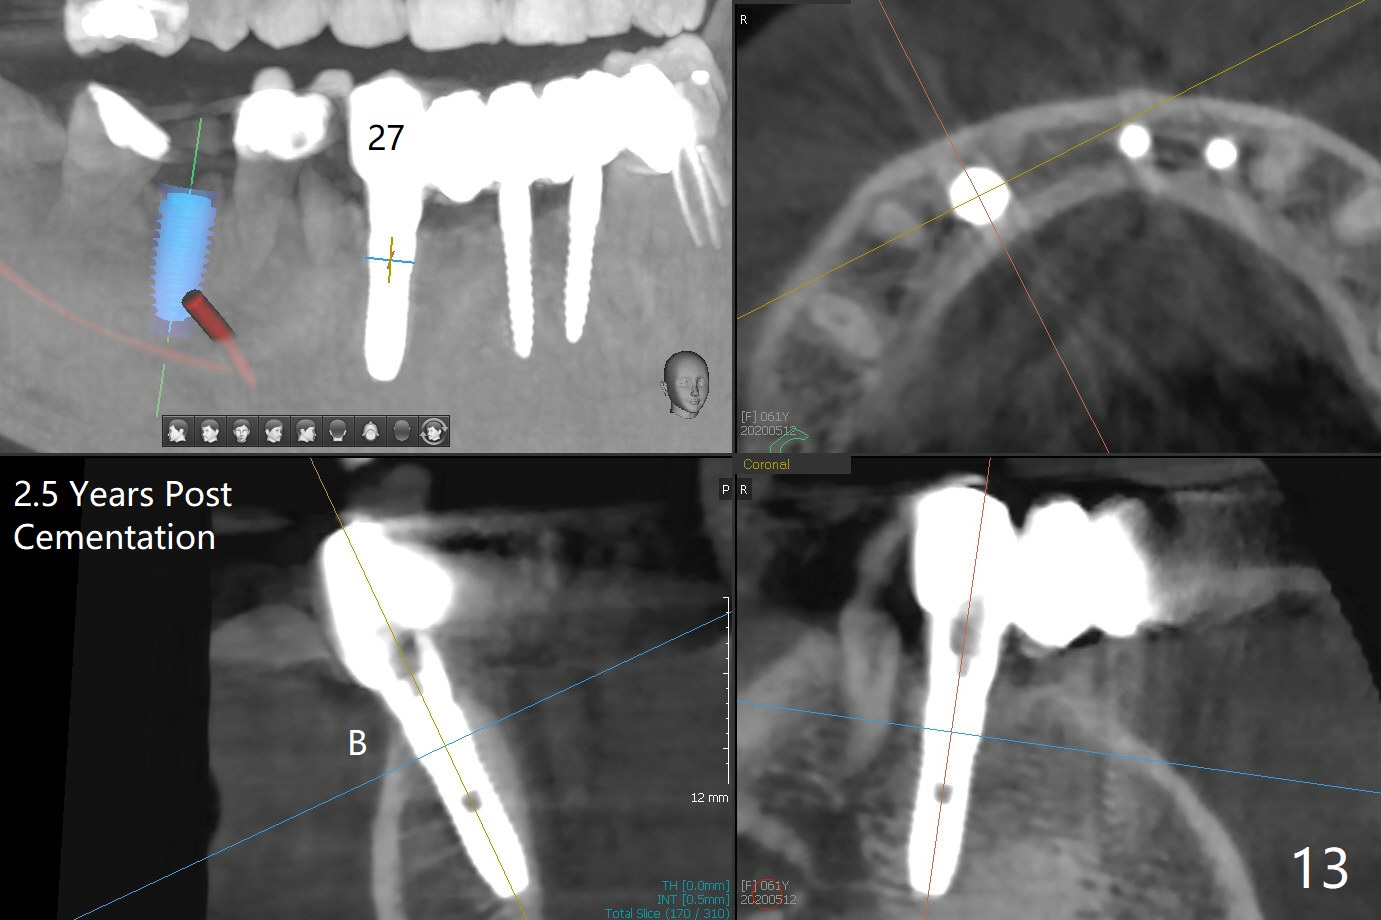

There is severe buccal gingival recession at #27 (Fig.1 arrow), as compared to that at #22. After removing the bridge and extraction of #27 (Fig.2 with severe loss of the buccal plate), a 3x18 mm drill is used to finish osteotomy (Fig.3). A 3.8x13 mm UF implant (Fig.3 green line) will be placed with 9 mm in the apparently solid, native (new) bone (blue line), while the coronal 5 mm will be occupied by the 5 mm cuff of a cemented abutment (pink line). The white dashed line is the gingival margin. The osteotomy is initiated as lingual as possible so that there will be at least 2 mm buccal gap when the narrow implant is placed. In spite of effort and precaution (guided surgery could control the trajetory), the coronal end of the implant tilts buccally so that a 4.5 mm 15 ° A 4 mm angled abutment is placed slightly subgingival (except buccal; Fig.5 A).

The mesial defect at #27 appears to have been repaired 8 months postop (Fig.8,9 *); there is no bone loss at 1-piece implant sites. The gingival recession seems to remain the same before and after removal of the provisional FPD (Fig.10,11). The bulging abutment at the cervix is less prominent when a straight abutment is used and prepared (Fig.12, 4.5x5.5(5) mm). There is no bone loss at #23, 25 and 27 sites 2.5 years post cementation (Fig.12-15), although the trajectory of the implants could be improved by using surgical guide (Fig.16-18).